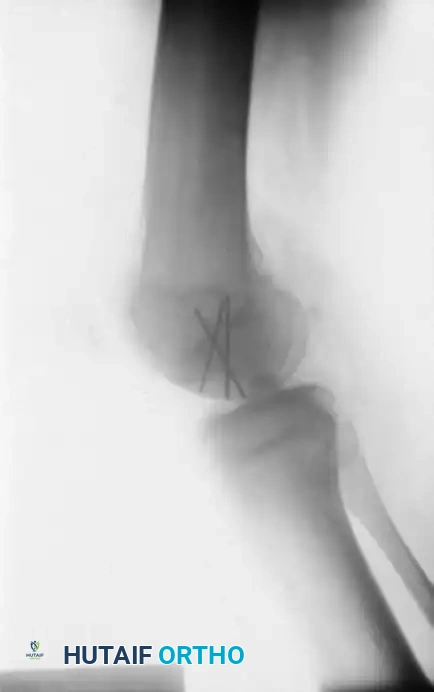

Image

The radiographic series above illustrates a 15-year-old boy with a large osteochondritis dissecans lesion involving the weight-bearing portion of the lateral femoral condyle. The fragment was successfully reduced and internally fixed with multiple Kirschner wires. While K-wires provide excellent temporary fixation, they require subsequent removal. Modern practices frequently utilize bioabsorbable compression screws to avoid a secondary hardware removal surgery, though metallic screws remain the gold standard for maximal compression.

Surgical Warning: When using bioabsorbable implants, ensure the heads are countersunk at least 1-2 mm below the articular surface to prevent opposing "kissing" lesions on the tibial plateau during the degradation phase.